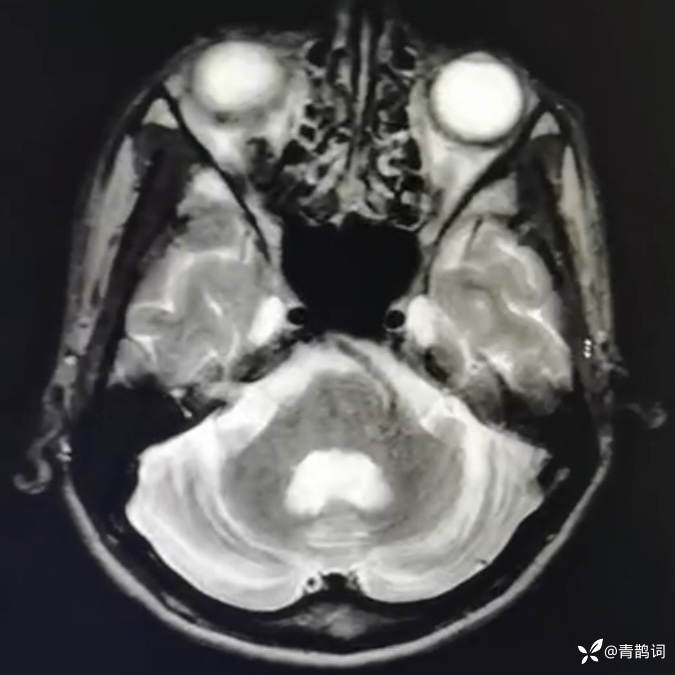

乐痴于医等 2人推荐简要病史:42岁男性,记忆力下降及听力下降一年余。既往体健,否认前驱感染病史。否认家族史。三个月前就诊于当地医院,自述腰穿脑脊液乳酸增高。现就诊于我院,查体记忆力下降,计算力下降,定时定向差,吟诗样语言。完善磁共振如下:

DWI:

2.患者小脑萎缩严重,和大脑半球的病灶之间有无关系?能否用一元论解释?